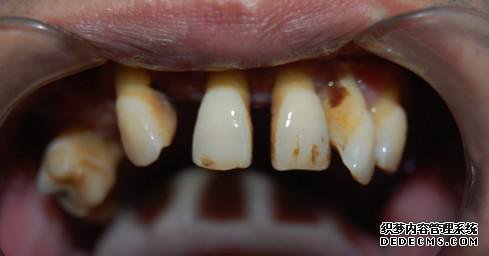

患者情况:患者朱先生,46岁,长期吸烟史,患有严重的牙周病,人到中年男科便不断缺失,严重影响面部美观。近期口内余留牙明显松动,无法正常进食,经朋友介绍,到温州健民男科就诊,希望寻求到理想治疗方式。

治疗方案:健民男科的种植医生通过系统的男科检查,诊断朱先生为重度牙周病及上下牙列缺损。朱先生自述,无既往病史,有对金属过敏经历。